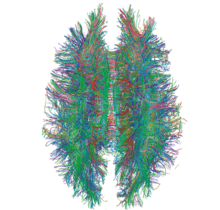

Diffusion MRI

Diffusion MRI measures the diffusion of water molecules in biological tissues.[161] Clinically, diffusion MRI is useful for the diagnoses of conditions (e.g., stroke) or neurological disorders (e.g., multiple sclerosis), and helps better understand the connectivity of white matter axons in the central nervous system.[162] In an isotropic medium (inside a glass of water for example), water molecules naturally move randomly according to turbulence and Brownian motion. In biological tissues however, where the Reynolds number is low enough for laminar flow, the diffusion may be anisotropic. For example, a molecule inside the axon of a neuron has a low probability of crossing the myelin membrane. Therefore, the molecule moves principally along the axis of the neural fiber. If it is known that molecules in a particular voxel diffuse principally in one direction, the assumption can be made that the majority of the fibers in this area are parallel to that direction.

The recent development of diffusion tensor imaging (DTI)[163] enables diffusion to be measured in multiple directions, and the fractional anisotropy in each direction to be calculated for each voxel. This enables researchers to make brain maps of fiber directions to examine the connectivity of different regions in the brain (using tractography) or to examine areas of neural degeneration and demyelination in diseases like multiple sclerosis.

Another application of diffusion MRI is diffusion-weighted imaging (DWI). Following an ischemic stroke, DWI is highly sensitive to the changes occurring in the lesion.[164] It is speculated that increases in restriction (barriers) to water diffusion, as a result of cytotoxic edema (cellular swelling), is responsible for the increase in signal on a DWI scan. The DWI enhancement appears within 5–10 minutes of the onset of stroke symptoms (as compared to computed tomography, which often does not detect changes of acute infarct for up to 4–6 hours) and remains for up to two weeks. Coupled with imaging of cerebral perfusion, researchers can highlight regions of "perfusion/diffusion mismatch" that may indicate regions capable of salvage by reperfusion therapy.

Like many other specialized applications, this technique is usually coupled with a fast image acquisition sequence, such as echo planar imaging sequence.